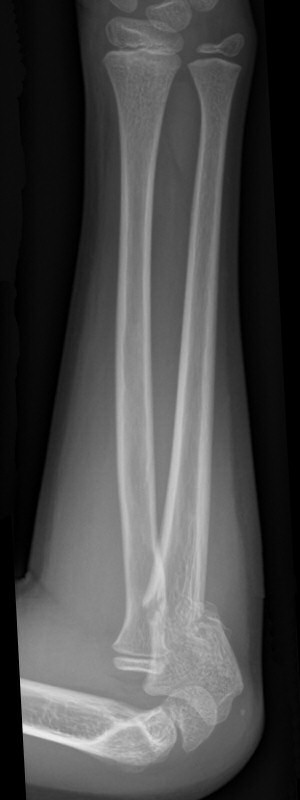

Distala diafysära radius- och ulnafrakturer, opererade med TEN-spikar, sista bilderna läkt efter 7 månader. Alla bilderna är från samma patient.